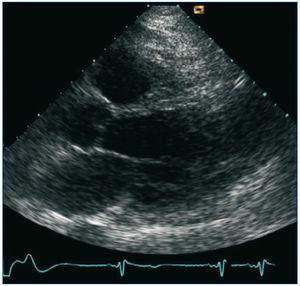

En el ecocardiograma realizado al día siguiente al ingreso se objetiva aquinesia de septoinferior, cara inferior y del tercio distal de todas las caras, con aneurisma de los tercios distales de caras anterior y lateral; fracción de eyección del ventrículo izquierdo 35%; insuficiencia mitral ligera-moderada; insuficiencia tricúspide ligera (figura 2). En el Holter se confirma la existencia de numerosas extrasístoles ventriculares.

Figura 2. Ecocardiograma en el que se observa aneurisma ventricular